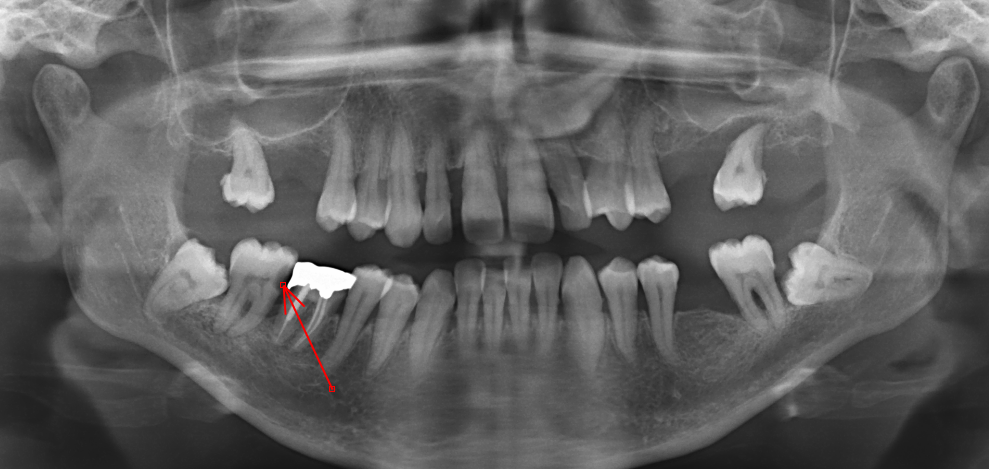

Parodontite

- Cause la plus fréquente de perte de dents

- Plaque dentaire > Gingivite > Destruction du ligament parodontal > Resorption osseuse

- Elargissement de l’espace du ligament parodontal

- Osteolyse

- Defaut de recouvrement des dents

Osteolyse (blanc), elargissement du ligament parodontal (noir)

Defaut de recouvrement dentaire

Pericoronite

- Inflamation au niveau de la couronne

- Peut se propager inférieurement et faire des abcès

Abcès Dentaire